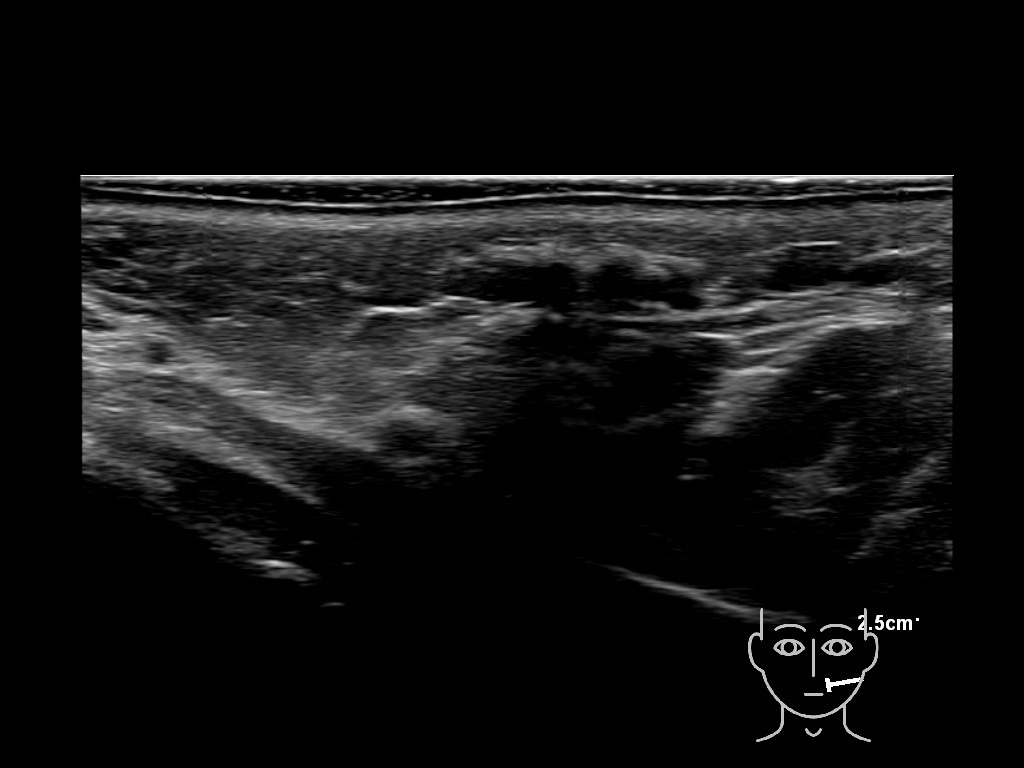

Fillers

Draw in the image on the right where the fillers are located. To check if your answer is correct, please click on the secondary image.